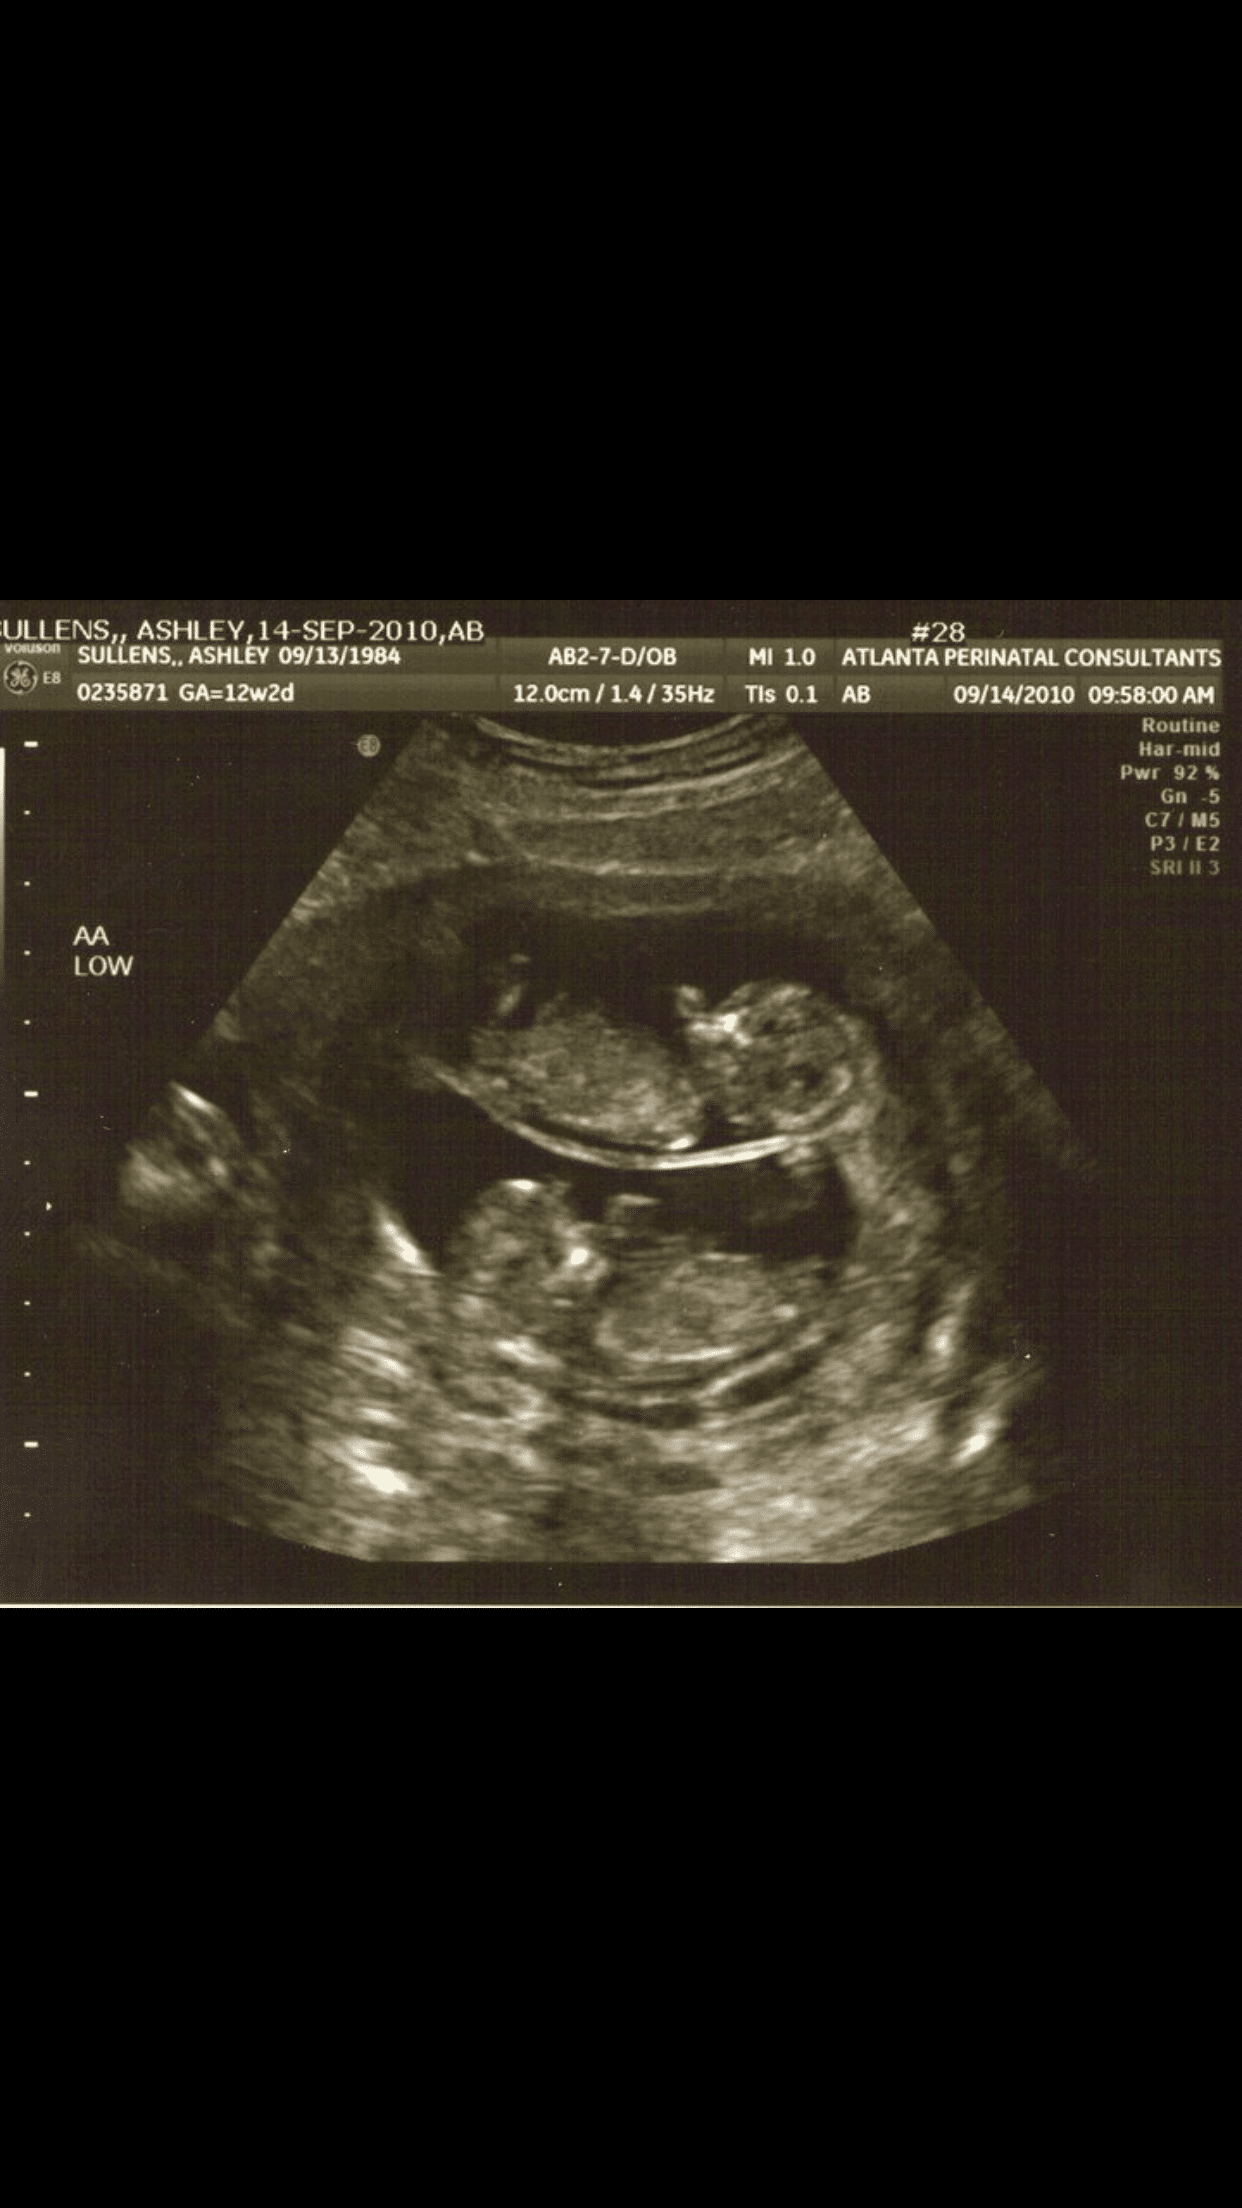

Ultrasound Photos at 12 Weeks Pregnant With Twins